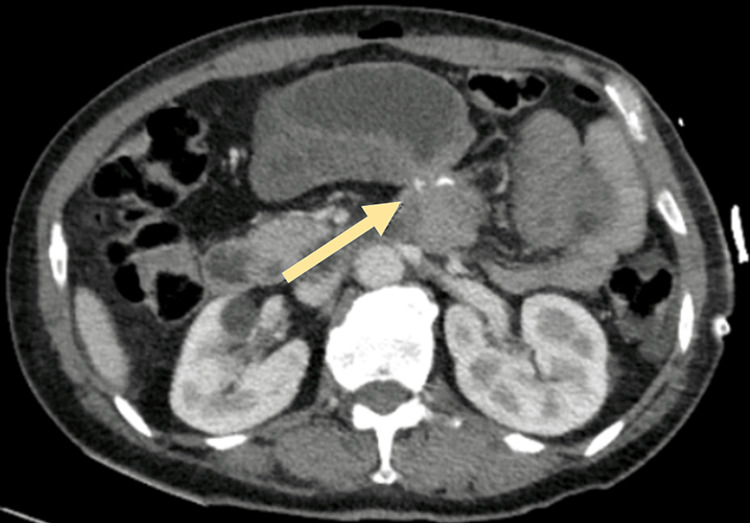

A 42-year-old female presented to the emergency department with intermittent diffuse abdominal pain with radiation to the left flank, nausea, and vomiting within one day of evolution. No genitourinary symptoms were reported. No bowel movements were reported in the previous four days. Three days before, the patient underwent an abdominoplasty with rectus plication and the procedure was uneventful. She has a history of laparoscopic gastric bypass (Roux-en-Y), 2,5 years before, after which the patient complained of chronic abdominal discomfort related to food intake. Blood tests showed normal hemoglobin, without leukocytosis, with mild elevation of C-reactive protein (2,7). CT Scan showed gastric, duodenum, and jejunal distension; with parietal thickening, wall heterogeneity, and mucosal hypercaptation in the proximal jejunal loop; a stop point in the proximal jejunum and rotation of mesenteric vessels, suggesting an internal hernia (Figure 1).

Figure 1. CT scan showing the abrupt stop sign in a proximal jejunal loop.